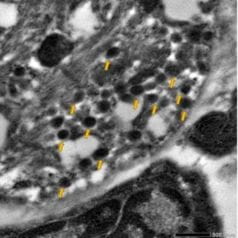

- "Advanced Imaging Techniques for the Characterization of Subcellular Organelle Structure in Pancreatic Islet β Cells." Published in Comprehensive Physiology. Contributing IU authors: Madeline R. McLaughlin, Staci A. Weaver, Farooq Syed, Carmella Evans-Molina